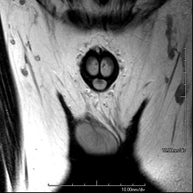

Prueba diagnóstica no invasiva que consiste en la obtención de imágenes de alta definición anatómica de la pelvis mediante el empleo de un campo electromagnético y ondas de radio (con un emisor y un receptor). No utiliza radiación ionizante. Se realiza para estudiar patologías del útero, del ovario, de las trompas y la vagina, ya sean de origen tumoral, inflamatorio o vasculares. Además permite valorar les estructuras adyacentes localizadas en la pelvis, identificando sus alteraciones. A veces requiere el uso de contraste intravenoso (Gadolinio) para caracterizar las lesiones. - RM Pelvis masculina

Prueba diagnóstica no invasiva que consiste en la obtención de imágenes de alta definición anatómica de la pelvis masculina mediante el empleo de un campo electromagnético y ondas de radio (con un emisor y un receptor). No utiliza radiación ionizante. No requiere de preparación previa. En algunas ocasiones requiere el empleo de contraste paramagnético (Gadolinio) para caracterizar las lesiones. Esta prueba permite valorar órganos como la vejiga urinaria, la unión entre los uréteres y la vejiga, la próstata, las vesículas seminales, la uretra, los huesos de la pelvis, etc.